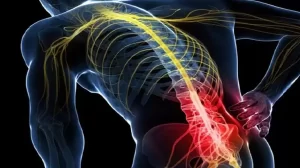

آسیبهای ستون فقرات و نخاع: دلایل، عوارض، روشهای تشخیص و درمان

آسیبهای ستون فقرات و نخاع میتوانند به دو دسته اصلی تقسیم شوند: شکستگی مهرهها و دررفتگی مهرهها. شکستگی به معنای شکستن یک یا چند مهره

درمان قطعی سیاتیک: روشهای جراحی و غیرجراحی

سیاتیک یا رادیکولوپاتی سیاتیک، درد ناشی از فشار یا تحریک عصب سیاتیک است که از ناحیه کمر شروع و تا باسن، ران، ساق و کف